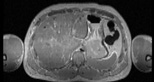

Visible Human male: Sectio transversalis 1524

CT

NMR

Pd                          / T2 \                         T1